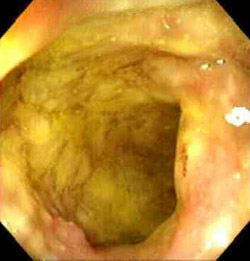

На фото воспаление кишечника при энтероколите